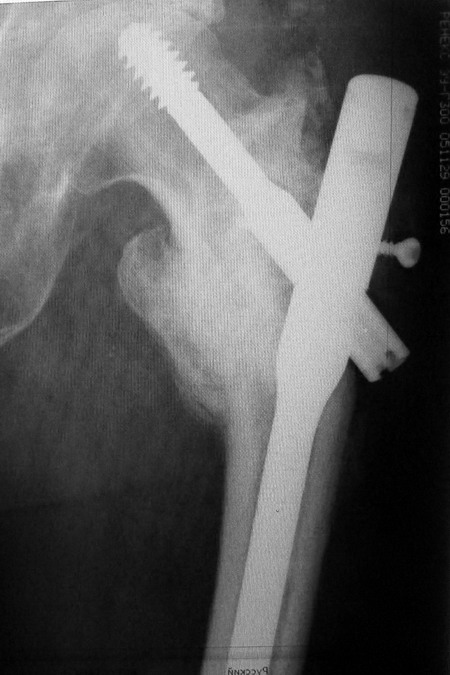

Так стало после реостеосинтеза - два снимка непосредственно сразу после

операции, последний снимок - через 6 мес. Пациент свободно ходит.